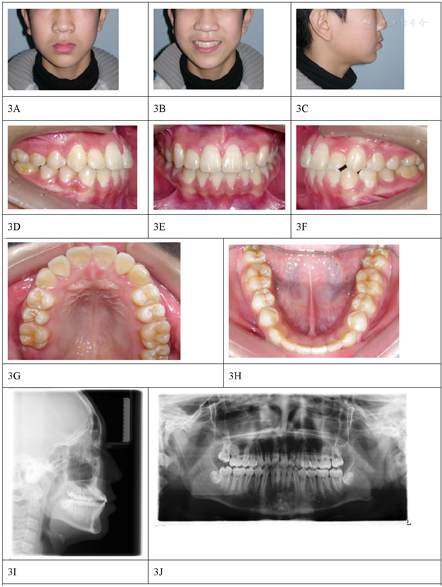

面部正面观,左右对称,面上中下1/3比例尚可。侧面观,凹面型,上颌后缩,下唇稍前突。正面微笑上切牙暴露不足。口内检查:替牙列晚期,上颌双侧第二乳磨牙以及左下第二乳磨牙未脱落,右下第二前磨牙萌出中,替牙间隙存在。磨牙中性关系,前牙浅反覆合,左侧后牙反合。上牙列严重拥挤,双侧侧切牙腭向错位无间隙,下牙列中度拥挤(图1)。患者轻微张口,下颌未能后退达到切对切咬合。

全景片:上颌下颌第二前磨牙未萌出,牙根发育约1/2,颞下颌关节髁突情况尚可,可见下颌第三磨牙牙胚影像。头颅侧位片(图1)头影测量SNA角(蝶鞍点、鼻根点与上牙槽座点构成的角)为75.8°,ANB角(上牙槽座点、鼻根点与下牙槽座点构成的角)为-3.8°,MP-FH(下颌平面与眶耳平面夹角)为24.1°。

本例诊断为骨性Ⅲ类,上颌后缩(替牙列期),牙列拥挤(替牙列期)。